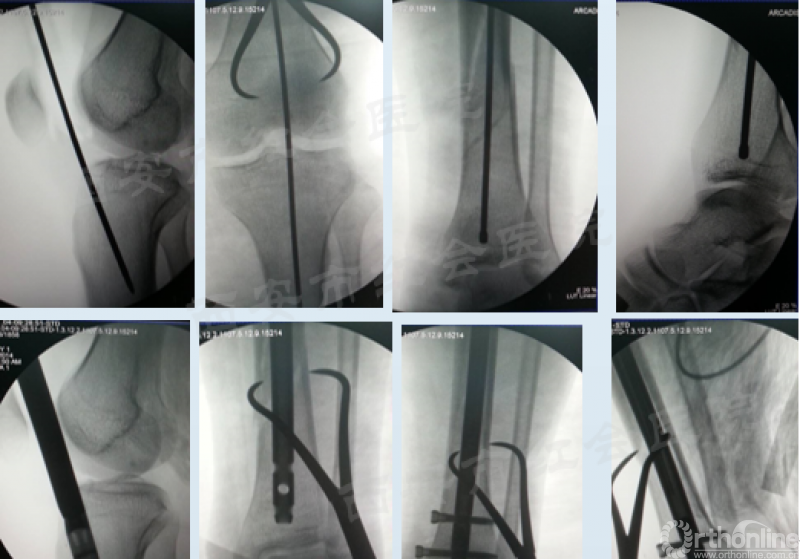

髌外侧入路

仰卧于可透视手术床,铺巾前小腿下垫楔形垫。沿髌骨、髌腱外侧做一长约5cm的弧形切口,切开髌腱外侧支持带,牵开并保护脂肪热,触摸入点,克氏针定位,透视证实,用套筒将髌骨和髌腱往内侧推移,开口,置入导针,随后对骨折进行复位,再按照标准流程植入髓内钉。

经典病例展示

(图片滑动展示)